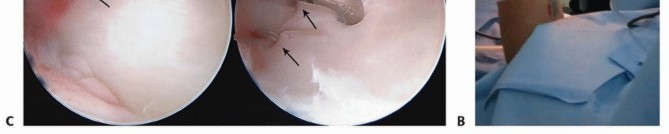

Arthroscopic Triangular Fibrocartilage Complex Repair It should be noted that while this procedure can be used for the treatment of Galeazzi fracture-dislocations, the procedure and outcomes have not been rigorously evaluated in published literature. The surgeon is seated facing the monitor. Finger traps are placed on the index and long fingers, and a 15-pound traction is applied (TECH FIG 3A,B). Three portals are needed for arthroscopic TFCC repair (3-4 visualization, 4-5 working, and 6U outflow). Skin markings of the bony anatomy (radial styloid, ulnar styloid, Lister tubercle) and planned portals are made prior to inflating tourniquet. To establish the 3-4 portal, the soft spot approximately 1 cm distal to Lister tubercle is marked. Insert an 18-gauge needle, angled to match the sagittal tilt of the distal radius, and inject 4 mL of saline (or 1% lidocaine with 1:100,000 epinephrine) to insufflate the radiocarpal joint. A 4-mm skin incision is made at the planned portal site, and blunt dissection to the level of the capsule with a mosquito is performed. A blunt trocar is used to penetrate the joint capsule and avoid cartilage injury, and a 1.9-mm camera is then inserted into the radiocarpal joint. Outflow is established at the 6U portal with insertion of an 18-gauge needle ulnar to the ECU into the ulnocarpal joint.

---

TECH FIG 3 • Wrist arthroscopy to address TFCC injury. A. The patient is placed supine with an arm board; a strap is used to securely fashion the arm to the table. A boom is placed on the contralateral side. B. Finger traps are positioned, the weight is attached. Fluoroscopy is used to access DRUJ reduction. C. TFCC Palmar 1B injury is present and repaired in this case with two horizontal mattress sutures. The 4-5 working portal is established using the same steps as the 3-4 portal. Next, a probe is inserted through the 4-5 portal to examine the integrity of the TFCC. In a Galeazzi fracture-dislocation, a foveal avulsion is present (Palmer 1B), and the tear is easily recognized. To begin TFCC repair, a 2-mm shaver is placed through the 4-5 portal, and unstable tear edges are débrided. Next, a 2-cm longitudinal skin incision is made over the medial distal ulna and blunt dissection proceeds to the bone. A 0.062-inch smooth stainless steel pin is placed obliquely from medial ulna to fovea and directly visualized arthroscopically entering the fovea. The pin is then overdrilled (outside-in) with a 3.0-mm cannulated drill bit. A sharp-tipped suture passer loaded with nonabsorbable suture is passed through the bone tunnel (outside-in), piercing the TFCC at the desired location. Suture is then passed around the TFCC into the joint and retrieved out of the 4-5 portal with a suture grasper. Another sharp-tipped suture passer loaded with a looped Nitinol wire is then passed through the ulnar bone tunnel to penetrate the TFCC at a different location. The looped Nitinol wire is retrieved through the 4-5 portal and used to retrieve the previously passed suture out the bone tunnel, thus creating a mattress stitch through the TFCC (TECH FIG 3C). Traction is placed on the suture to evaluate the repair. Additional sutures may be passed as needed. Prior to tying down the sutures, two 1.6- or 2.0-mm smooth stainless steel pins are placed across the radioulnar joint as previously described. Finally, a drill hole for a bioabsorbable suture anchor is created proximal to the bone tunnel on the medial edge of the ulna. The sutures are placed through the anchor, and tension is placed while directly visualizing the TFCC. The suture anchor is then inserted. Wound closure, sterile dressings, and long posterior splint are applied.